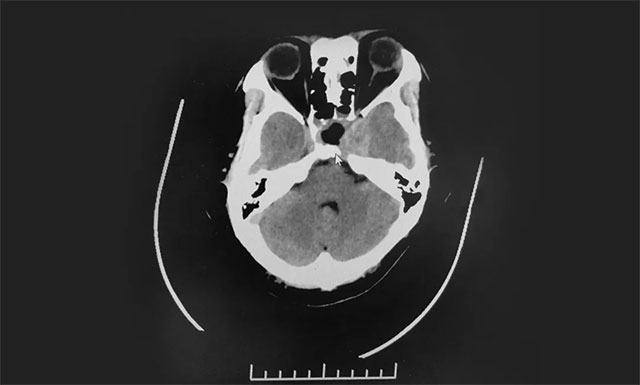

在制定詳細(xì)手術(shù)方案并充分完善術(shù)前準(zhǔn)備后,7月24日,李士其教授在吳治群博士、黃秀夫醫(yī)生協(xié)助下經(jīng)蝶竇入路成功為患者進(jìn)行了手術(shù)。術(shù)中,在蔡司顯微鏡(雙熒光)下,見淡紅色腫物,質(zhì)軟,其外有包膜覆蓋。李士其教授在充分保護(hù)好海綿竇、頸內(nèi)動脈、視神經(jīng)等結(jié)構(gòu)前提下,將鞍內(nèi)可見腫瘤全部切除,并留取腫瘤送檢病理。手術(shù)順利完成,術(shù)中只失血約10毫升。

目前,患者視力明顯改觀。后期還將輔以藥物及放射治療。